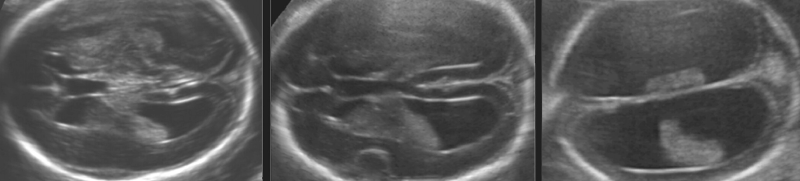

Επικοινωνία Ραντεβού Απαιτούμενες ΕξετάσειςΡαντεβούΡαντεβού, παραπομπή εγκύων και απαιτούμενες εξετάσεις